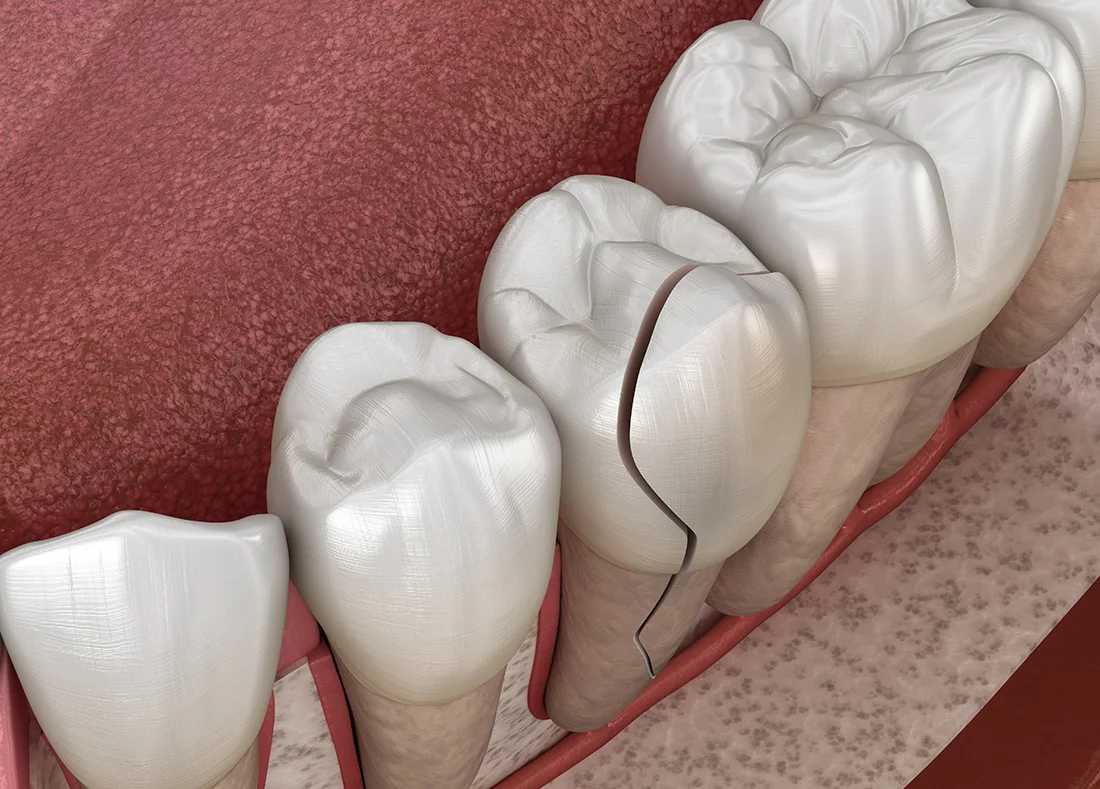

Even a small chip or crack can lead to bigger problems if left untreated. Rinse your mouth with warm water and apply a cold compress to reduce swelling. Avoid biting down or chewing on the affected side. If you’re in pain or notice sharp edges irritating your tongue or cheek, let us know. We’ll examine the damage and recommend the most effective repair—whether it’s bonding, a crown, or another restorative option.